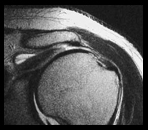

Shoulder

- Rotator cuff tendinosis and tears